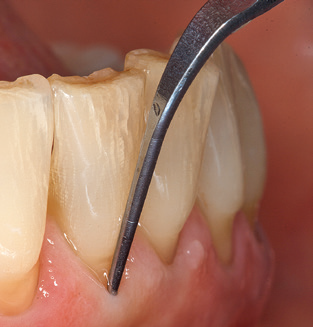

Fig. 4: Flexible probes with millimetre markings are recommended for the probing of dental implants (e.g. Colorvue Kit PCV11KIT6, Hu­Friedy). – Fig. 5a and b: A straight working tip (1P, W&H Dentalwerk Bürmoos GmbH) is a suitable instrument for use on all natural teeth. – Fig. 6: Curved working tips (3Pr/3Pl, W&H Dentalwerk Bürmoos GmbH) lend themselves to the processing of difficult-to-reach areas of the tooth and root surfaces (e.g. furcations). – Fig. 7: The tapered, hexagonal implant cleaning tip (1I, W&H Dentalwerk Bürmoos GmbH) permits atraumatic and efficient cleaning of the crown and abutment surfaces. – Fig. 8: Titanium and carbon curettes are suitable instruments for the manual cleaning of the implant surfaces.

Of course, working tips for the cleaning of implant surfaces are also indispensable for SPT in patients fitted with implants. The implant cleaning attachment on the system used here is characterised by its tapered, hexagonal design. This design allows light, atraumatic penetration of the peri-implant pocket and displays a good cleaning performance (Fig. 7).